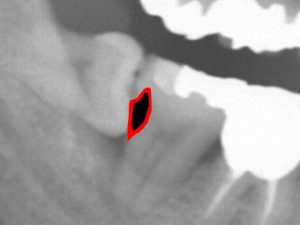

虫歯で歯が溶けた部分を黒く表示してみます。

実際の虫歯はレントゲン上で黒く見える部分だけではありません。

実際の虫歯はもっと大きく黒く見える部分より一回り大きいことがほとんどです。

以下の赤色部分程度に大きい可能性が高いです。

かなり深い位置まで虫歯があるのです。